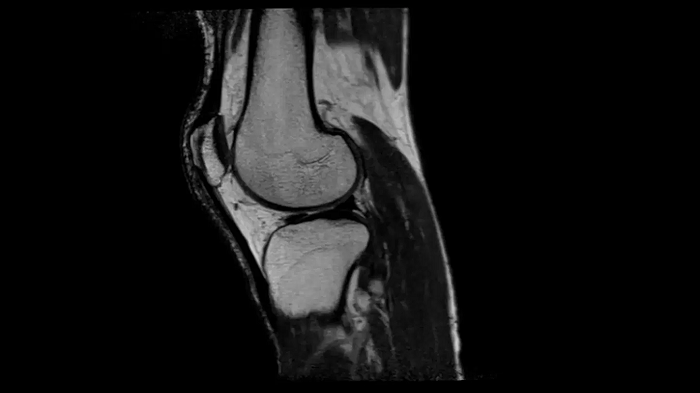

Knee

PD TSE Fat Sat with Deep Resolve and Simultaneous Multi-Slice

For clear imaging of the knee, outstanding fat suppression and performance are possible. Integrating the influence of Deep Resolve with the established Simultaneous Multi-Slice technique.

SMS 2 | Deep Resolve Gain & Sharp

0.4 x 0.4 x 3.0 mm2

TA 2:56 minutes

T1 SE

Outstanding T1 imaging of the knee using MAGNETOM Free.Star.

0.3 x 0.3 x 3.0 mm2

TA 2:54 minutes